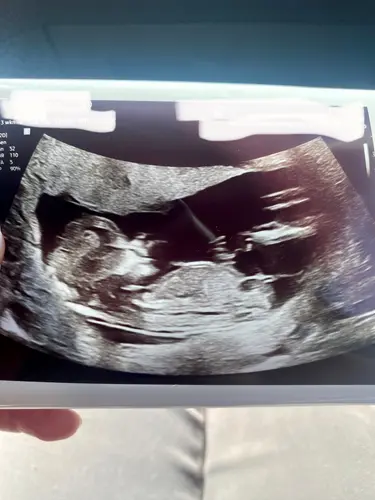

Fijn nieuwe topic! De vorige was veel scrollen ;p heb al van twee dames hier begrepen wat zij denken van mijn nieuwe echo foto maar toch benieuwd wat meerdere dames denken?